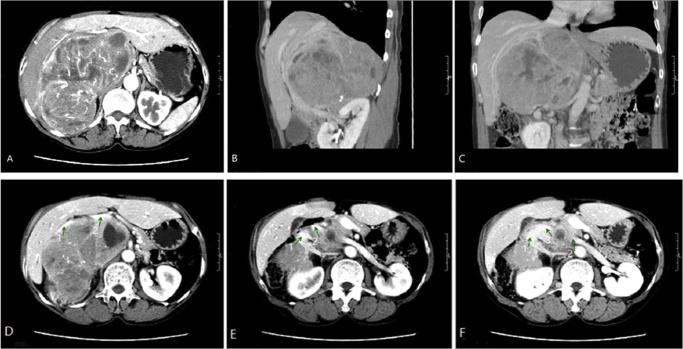

一名57岁女性在经过充分的术前药物准备后,因巨大嗜铬细胞瘤(16×15×10厘米)接受了择期开放手术。在肿瘤游离过程中患者出现严重高血压,肿瘤切除时出现危及生命的低血压。血流动力学不稳定得到成功处理。组织学检查显示为嗜铬细胞瘤,切缘无肿瘤残留。患者术后完全康复,高血压完全缓解。